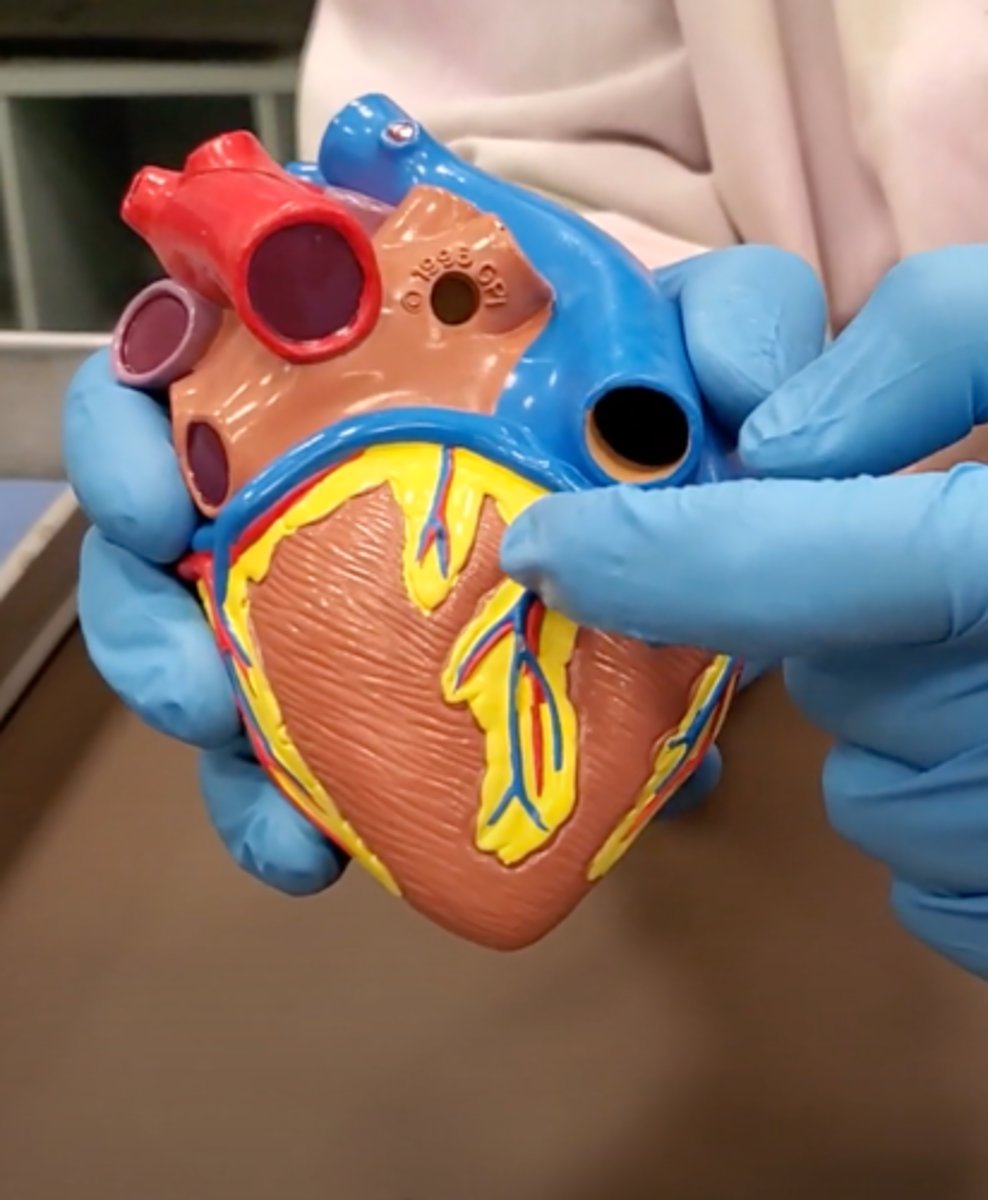

pulmonary trunk (model)

yellow sash of fat that tells you this if the front side of the heart (model)

t-shaped ribbon of fat on back side of heart (model)

Left ventricle (model)

has the most muscle mass because it has to pump blood to the whole body

apex (model)

base (model)

where everything connects